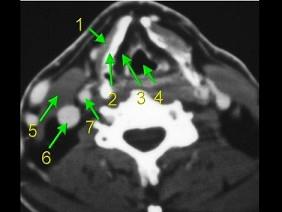

下面是一颈部CT图,其中结构标志不正确的是 ( )A、6为颈内动脉B、7为颈内动脉C、3为声门旁隙D、5为胸锁乳突肌E、2为甲状软骨

问题 下面是一颈部CT图,其中结构标志不正确的是 ( )

选项 A、6为颈内动脉 B、7为颈内动脉 C、3为声门旁隙 D、5为胸锁乳突肌 E、2为甲状软骨

答案 A